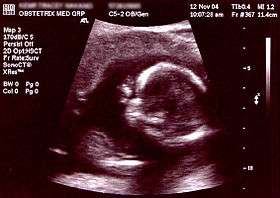

Obstetric ultrasound uses sound waves to produce pictures of a baby (embryo or fetus) within a pregnant woman, as well as the mother’s uterus and ovaries. It does not use ionizing radiation, has no known harmful effects, and is the preferred method for monitoring pregnant women and their unborn babies.